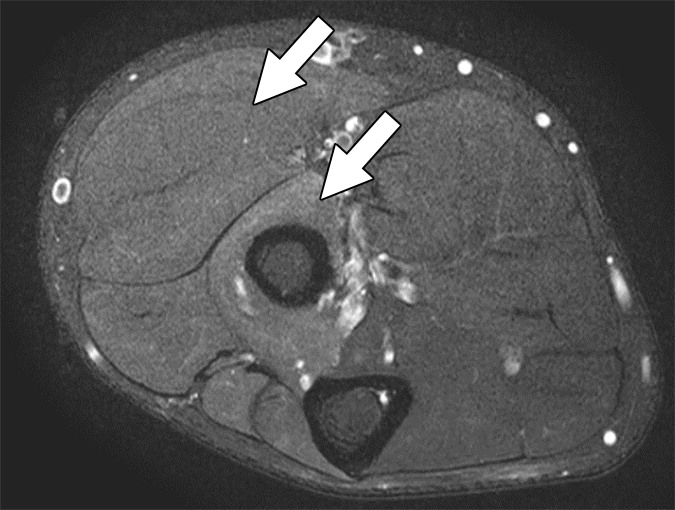

On the basis of the overall promising interrater agreement shown in this study, we believe that the newly proposed NS-RADS classification will perform as well in routine practice as it did in this initial validation study (Fig. 3).